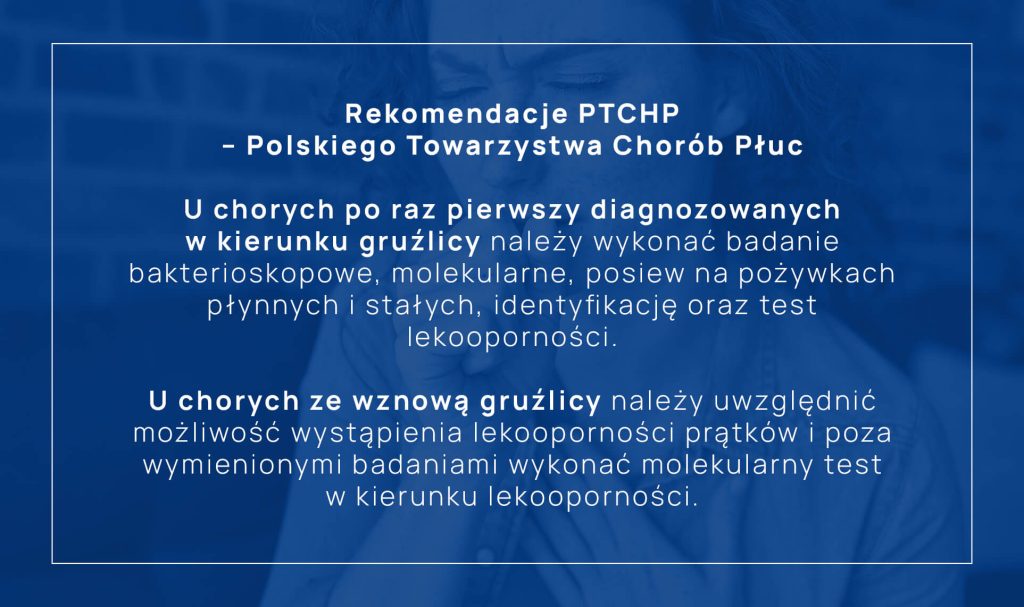

Polskie Towarzystwo Chorób Płuc na podstawie doświadczeń krajowych specjalistów oraz badań międzynarodowych przygotowało w 2013 r. zalecenia dotyczące rozpoznawania, leczenia i zapobiegania gruźlicy u dorosłych i dzieci. Jest to dokument, który w sposób wyczerpujący omawia problemy zawarte w tytule, poświęcając wiele uwagi prewencji. Czytelników zainteresowanych tematami odsyłamy do ww. rekomendacji.

Na podstawie wyniku bakterioskopii nie można ani potwierdzić, ani wykluczyć rozpoznania gruźlicy, ponieważ w dodatnim rozmazie mogą być obecne prątki środowiskowe. Przy dodatnim rozmazie należy wykonać badanie genetyczne (Rekomendacja PTCHP).

Badanie mikroskopowe i posiew na pożywkach hodowlanych (płynnych i stałych) muszą być wykonane w każdym przypadku podejrzenia gruźlicy, również przy dodatnim wyniku badania genetycznego (Rekomendacja PTCHP).